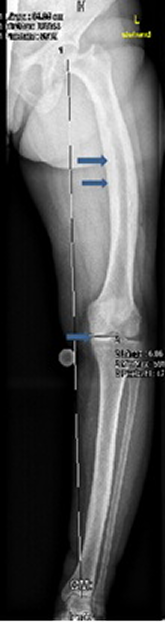

Sagittal T1-weighted MRI of the left knee showed no attachment of the posterior horn of the medial meniscus to the tibial plateau, but instead the meniscofemoral ligament (ligament of Wrisberg) joined the posterior horn of the meniscus to the lateral surface of the medial femoral condyle, i.e. discontinuity between the anterior and posterior horns, causing effectively the development of degenerative lesion of the posterior horn of the left medial meniscus (Figure 1 [Fig. 1]). On the bases of skeletal survey, weight bearing anteroposterior left lower limb radiograph showed varus deformity of the left lower extremity and narrowing of the medial knee joint and narrowing of the hip joint as well associated with unusual cortical thickening and bone enlargement. The angles of the frontal plane alignment were measured according to Paley: mechanical lateral distal femoral angle (mLDFA) = 106°, medial proximal tibial angle (mMPTA) = 85°, and the distal tibial angle (mLDTA) = 93°. These measurements were compared to weight bearing full length radiographs, which are considered to be the standard of reference for planning corrective surgery. The lateral distal left femoral angle measured 106°, which means approximately 20° deviation from the norms (Figure 2 [Fig. 2]). Skull radiographs showed the cotton wool appearance, disorganized trabecular with areas of sclerosis which are poorly defined and fluffy. Widening of the diploic space and relatively indistinct outer table, and the frontal sinuses are enlarged. No hyperostosis of the skull base was noted. These findings reflect the underlying pathologic changes of osteoblastic repair and are usually pathognomonic (Figure 3 [Fig. 3]). The patient underwent laboratory investigations with blood and urinary tests. Serum bone alkaline phosphatase was high (four times greater than the normal value), which is reflective of the rapid new bone turnover. Other laboratory studies showed normal levels of calcium, phosphate, PTH and vitamin D levels.

The patien underwent diagnostic arthroscopy of the left knee and mid-shaft osteotomy of the left femur with acute correction against varus position by means of fixationas which was done by using a unilateral fixator (LRS, Biomet Company USA) (Figure 4 [Fig. 4]). Six months postoperative radiograph showed that complete healing was accomplished, and the fixator was removed. There was a dramatical improvement of the mechanical axis, though still minimal varus deviation exists (Figure 5 [Fig. 5]).